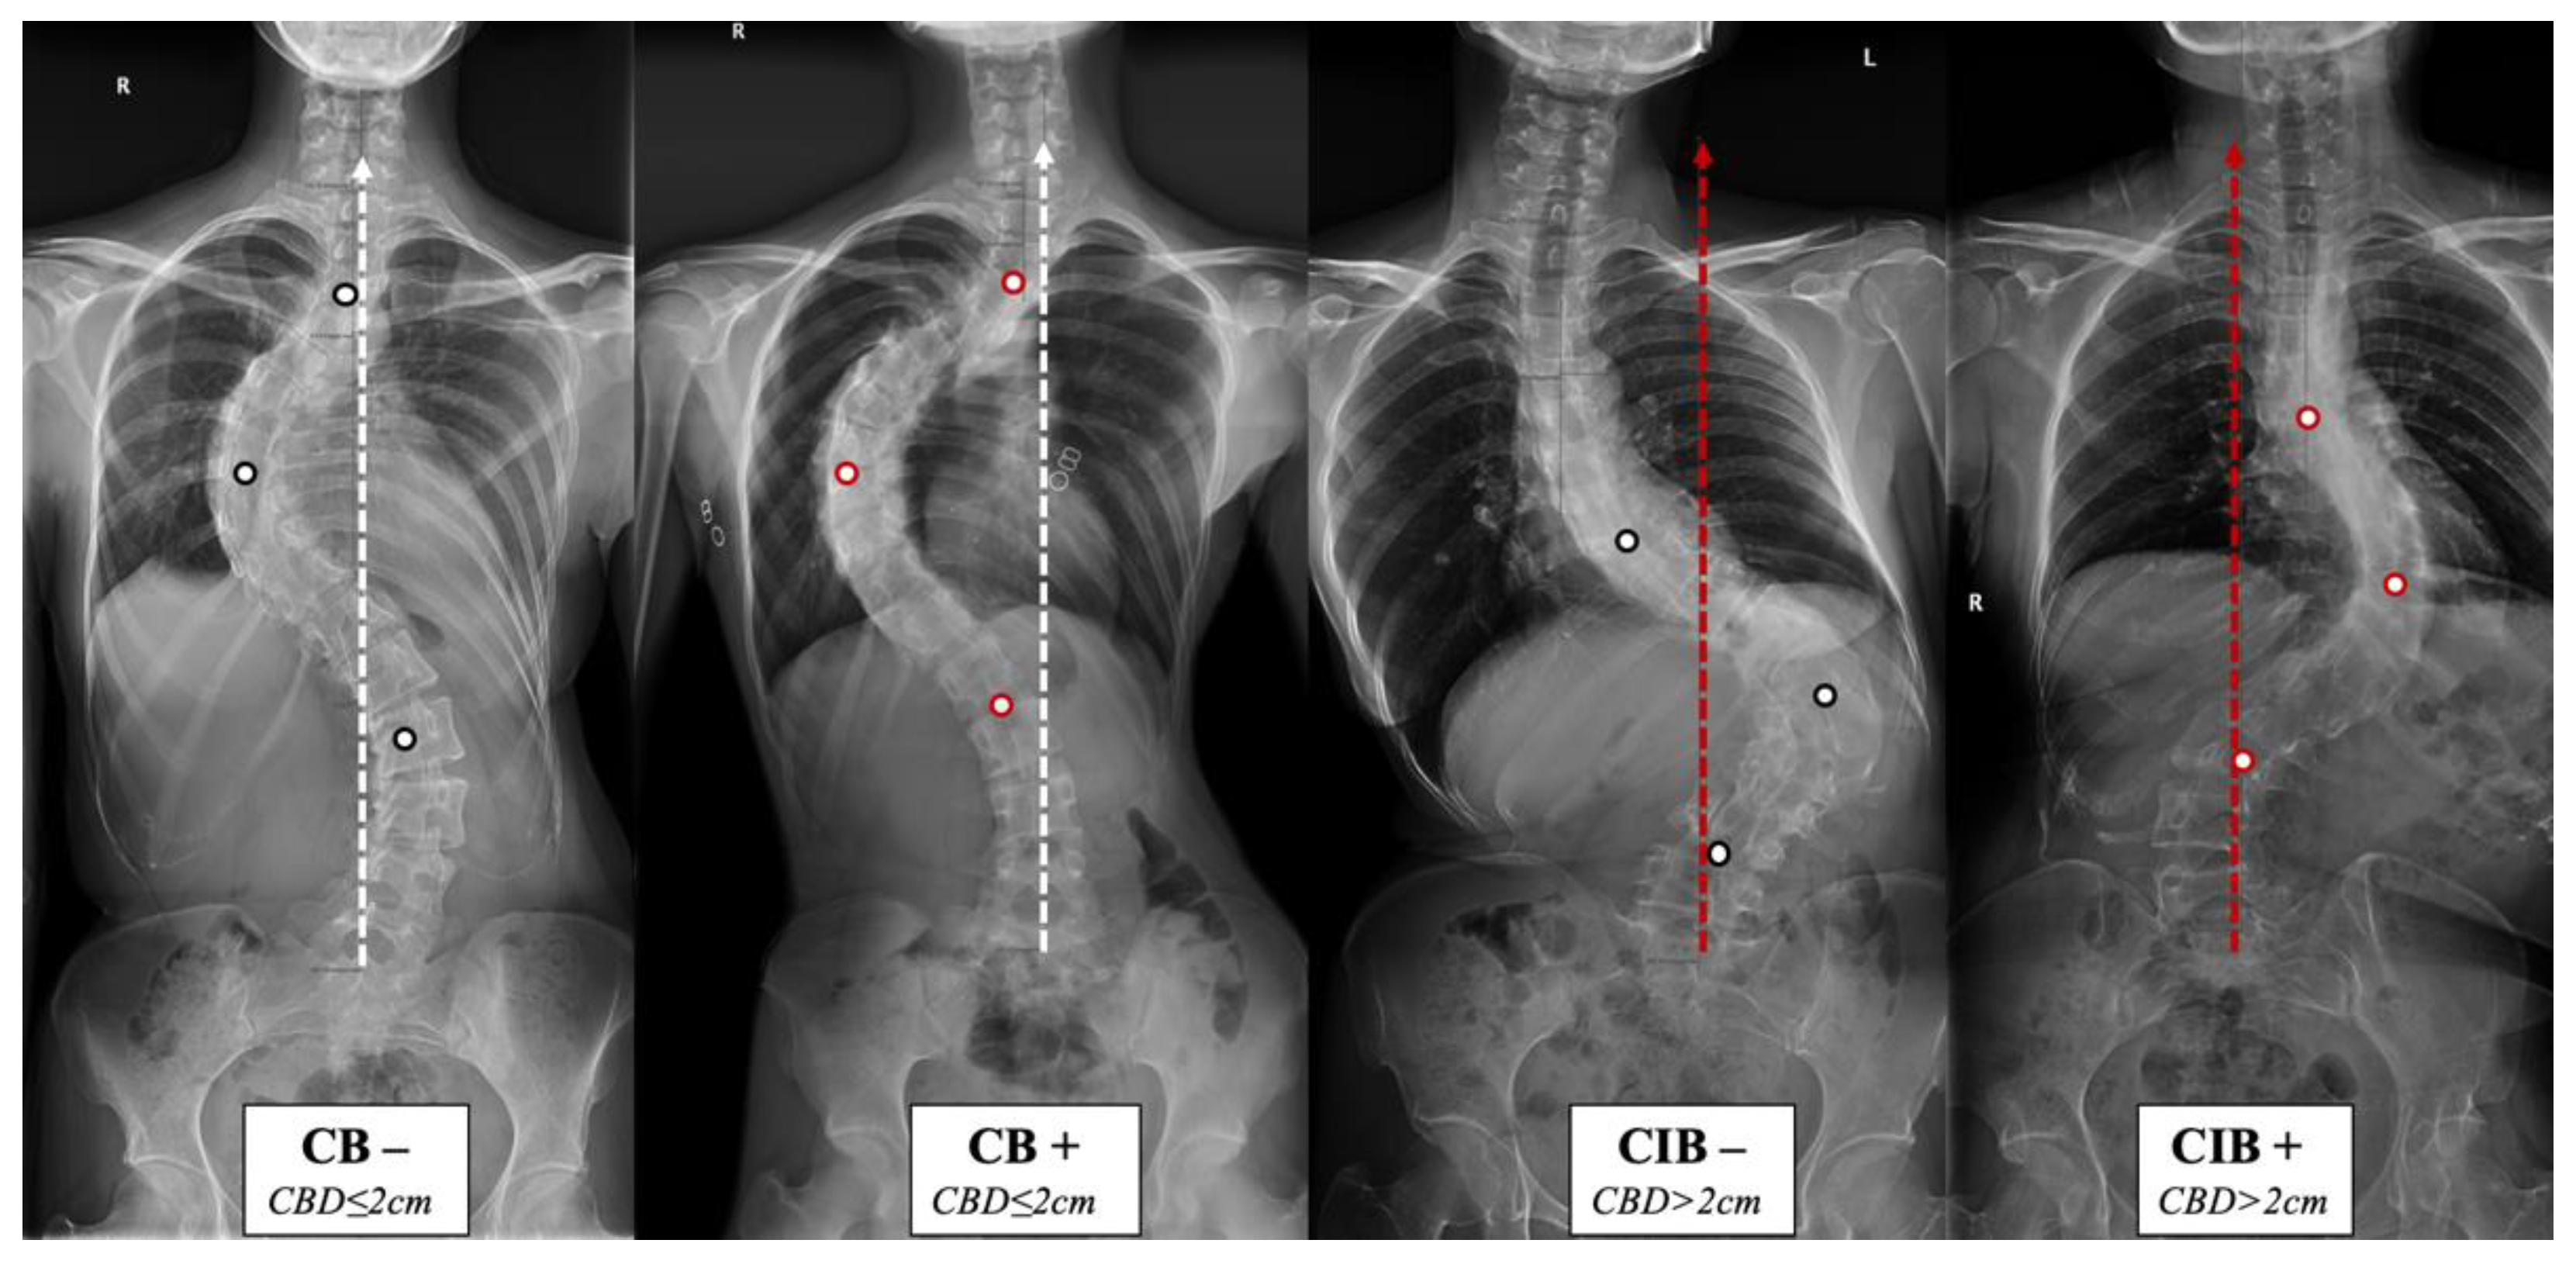

Figure 1.

Coronal balance classification of adult idiopathic scoliosis according to the standing anterior-posterior whole spine radiograph. The apical vertebras distribution modifier (+/−) is introduced to supplement the previous classification based on the coronal balance distance (CBD). CB is diagnosed if CBD ≤ 2 cm, and CIB is diagnosed if CBD > 2 cm. The apical vertebra modifier is defined as negative (−) when CoAVs are on either side of the CSVL. The apical vertebra modifier is defined as positive (+) when CoAVs are on the same side of the CSVL. The white dots represent CoAVs, and the dotted arrows represent the CSVL.

The apical vertebras distribution modifier is proposed in this study to supplement the coronal balance classification based on the positional relationship between the centers of the apical vertebras (CoAVs) and the CSVL (Figure 1 and Figure 2). The apical vertebra modifier is defined as negative (−) when CoAVs are on either side of the CSVL. The apical vertebra modifier is defined as positive (+) when CoAVs are on the same side of the CSVL.